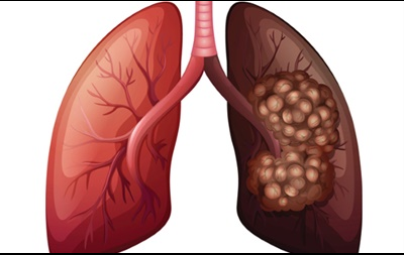

이번 기사에서는 폐암 초기 증상에 대해 자세히 정리해 알려 드리겠습니다 . 폐암은 국내암 사망률 1 위로, 과거에는 흡연이 폐암의 주된 원인 이었지만 , 현재는 비흡연 폐암 환자도 대폭 증가했습니다 . 폐암은 의학 기술로 발달하여 생존율이 높아지고 있습니다 . 폐암의 초기 증상은 무엇인가를 알아보겠습니다.